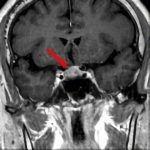

断層撮影

手術前1

手術前2